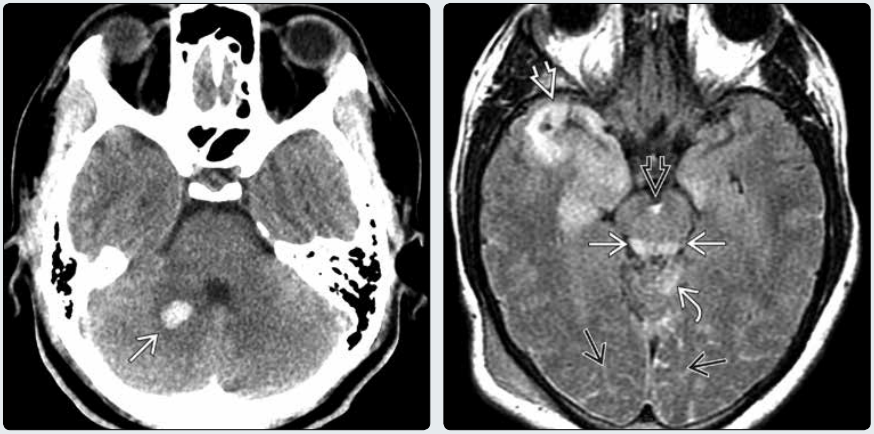

(左图)横断位 CT 平扫示右侧小脑中脚及小脑半球的高密度出血性皮层下弥漫性轴索损伤病灶→。

(右图)横断位 FLAIR 示顶盖的高信号皮层下损伤(本层面,下丘)→及邻近蚓部↪。另见右颞叶出血性脑挫伤➪以及多发脑沟裂 →和脚间窝的蛛网膜下腔出血➪

(左图)横断位 CT 平扫示双侧脑室内高密度的脉络丛实质内的脉络丛出血→。注意蛛网膜下腔出血➪,胼胝体 DAI➪,左侧尾状核出血性 DAI↪,以及脑室造瘘引流管尖端↪。

(右图)同一患者横断位 T2WI示低信号出血使脉络丛实质增大→。注意增大的右侧脉络丛出血使透明隔弯向左侧→。亦可见左侧尾状核出血性 DAI↪